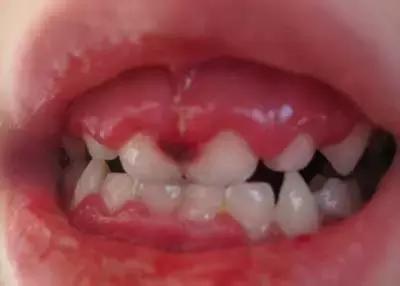

而手足口病的口腔溃疡位于腭弓前方、舌部和颊黏膜、少数位于唇龈沟和软腭及硬腭上,偶尔出现在悬雍垂、唇和扁桃体上。

(如下图)▼

疱疹性龈口炎患者不仅仅出现口腔内以及口唇的疱疹和溃疡,而且牙龈往往会红肿。部分口周有水疱。▼